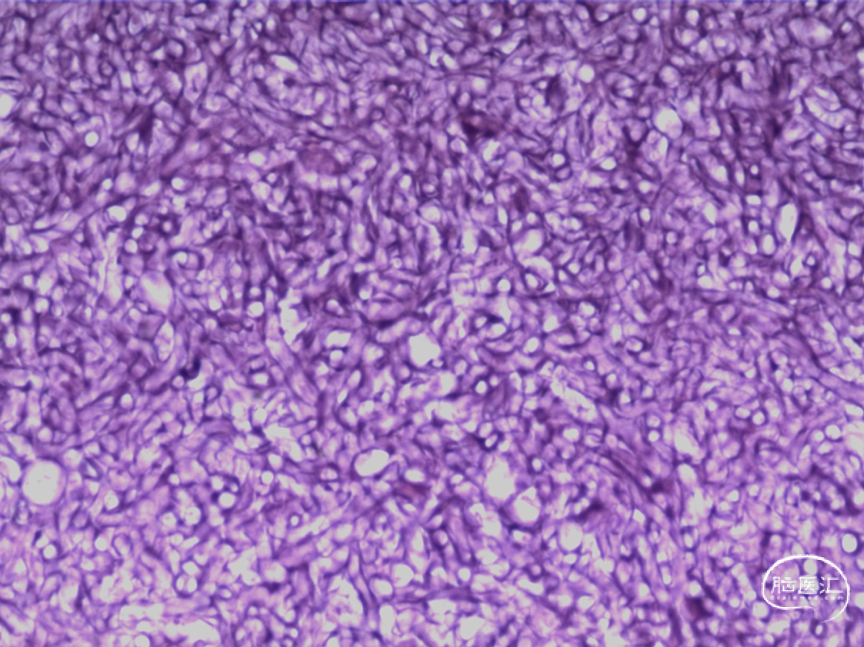

术后病理

可见典型曲霉菌菌丝及结构破坏: